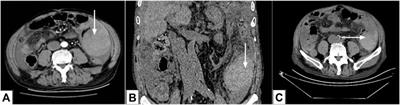

Cancer-associated thoracic aorta arterial thrombosis: case report and review of the literature